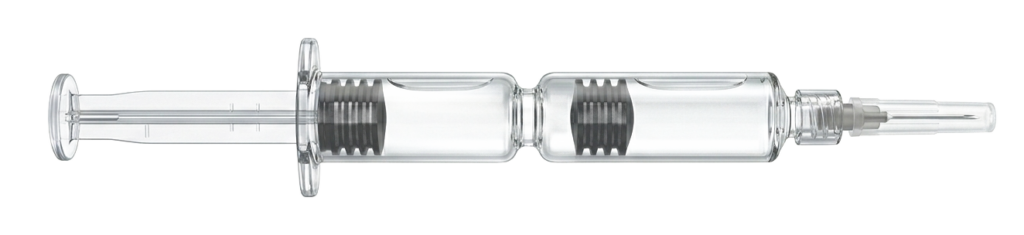

Eine mögliche Therapieoption ist die Injektion von Hyaluronsäure. Mit RenehaVis steht hierfür eine Doppelkammerspritze zur Verfügung, die zwei Hyaluronsäuren mit unterschiedlicher molekularer Struktur kombiniert. In einer Studie (letzte Seite) wurden 200 Patienten mit Kniearthrose durch RenehaVis behandelt. Ergebnis: Die Patienten berichteten von einer signifikant höheren Zufriedenheit im Vergleich zum Einsatz von Einkammerpräparaten.

Die spezielle Doppelkammerspritze ermöglicht die getrennte Applikation zweier Hyaluronsäure-Formen in einem Behandlungsschritt

- RenehaVis wird intraartikulär injiziert.

- Anwendung unter sterilen Bedingungen

- Optional ultraschallgestützt

- Einmalige Injektion gemäß Indikation